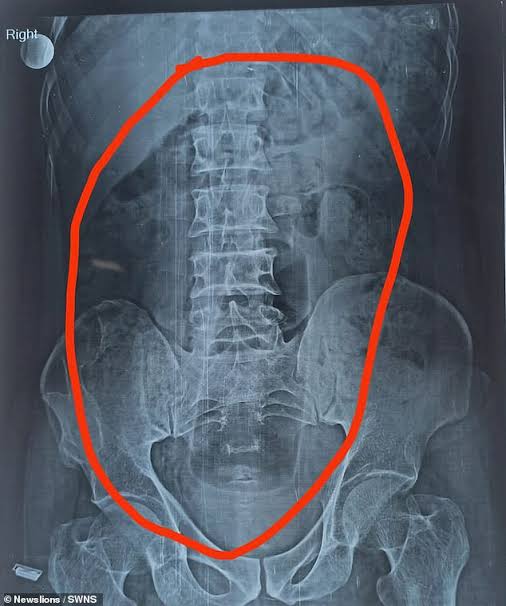

Meanwhile, an X-ray captured the bottle inside his abdomen before doctors were forced to intervene.